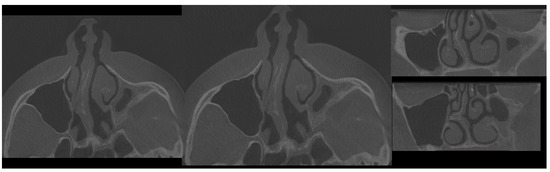

- Type 2 in-pure SSS (iSSS) (Figure 3, Figure 4 and Figure 6) related to maxillary deformation (might be related to maxilla-mandibular skeletal class II/III deformities or others), clinically asymptomatic, not related to trauma or surgery, 1–3 MS walls retracted, OMC clear, no opacification, like suggested by Lee et al., the “not so silent sinus” [18];